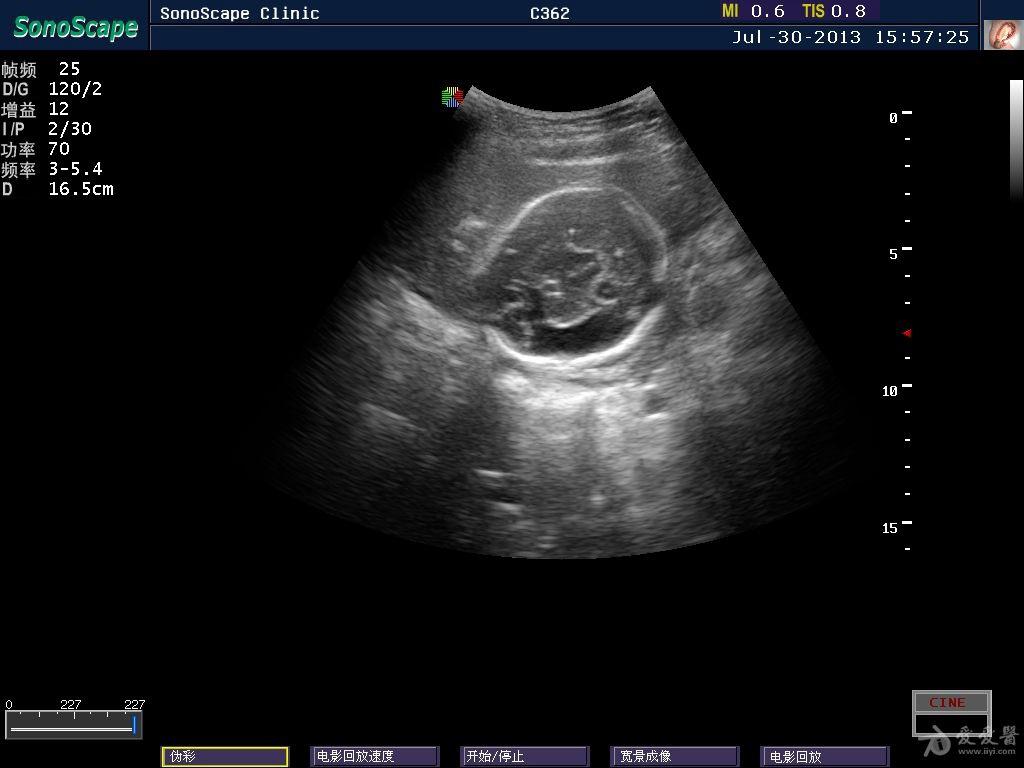

胎儿侧脑室超声图片,胎儿侧脑室测量图片

胎儿侧脑室增宽的超声诊断,评估和管理

胎儿侧脑室测量图片

侧脑室超声图像

胎儿侧脑室超声切面图

胎儿侧脑室正常值